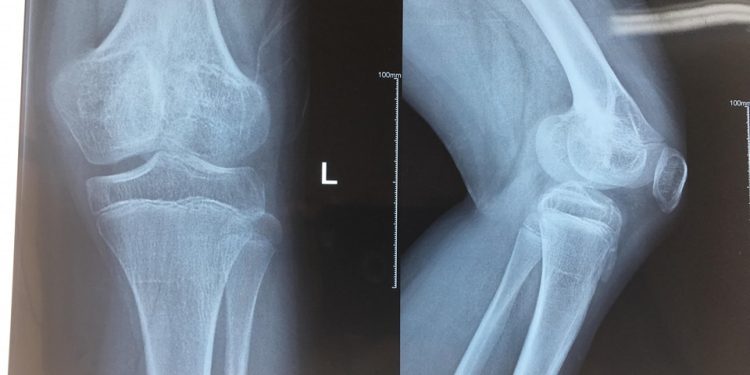

Phim chụp Xquang xương đùi của bệnh nhi trước mổ

Phim chụp Xquang xương đùi của bệnh nhi sau mổ